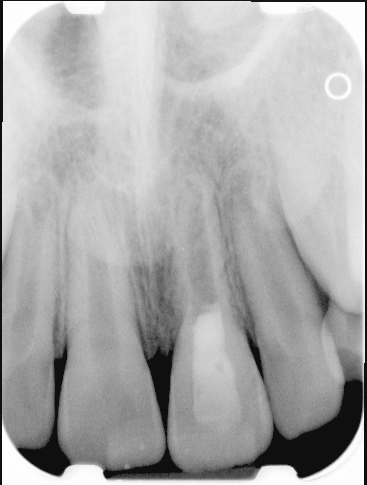

Fig 1. Preoperative radiograph showing apical bone loss.

Figure 1

Clinical procedure: If apical bone loss is present (Figure 1) a collagen/gelatin sponge (eg, Gelfoam®, Pfizer Inc., www.pfizer.com) can be placed apically so that the MTA can be delivered to the desired working length. (Any other surgical resorbable sponge would also work, such as OraPlug® [Salvin Dental Specialties, www.salvin.com], Surgifoam® [Midwest Dental, www.mwdental.com], or Surgispon® [Aegis Lifesciences, www.surgispon.com]). This is done by taking a small piece (2 mm x 2 mm) of the resorbable sponge and pushing it down to and through the root apex with an endodontic file. Once this is done, MTA is packed down the canal with a custom-fitted cone. The clinician can use a rubber stopper on the gutta-percha cone to know the exact length of MTA placed in the apical third (Figure 2). Once the apical third is sealed with 3 mm to 5 mm of MTA, the remaining coronal canal space can be back-filled using a warm gutta-percha technique (Figure 3).